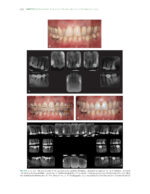

The Ortho-Perio Patient: Clinical Evidence and Therapeutic Guidelines 2019

کتاب افست ” The Ortho-Perio Patient: Clinical Evidence and Therapeutic Guidelines 2019 ” ویرایش اول